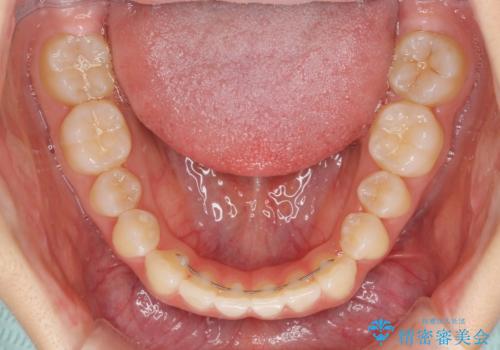

下顎の歯列が強く上顎に咬みこむことで隙間ができてしまうため、マウスピースの保定装置では後戻りのリスクが高くなってしまいます。

そのため、上下ともに前歯の裏側を細いワイヤーで固定し、その上から保定装置のマウスピースを使用していただくこととしました。